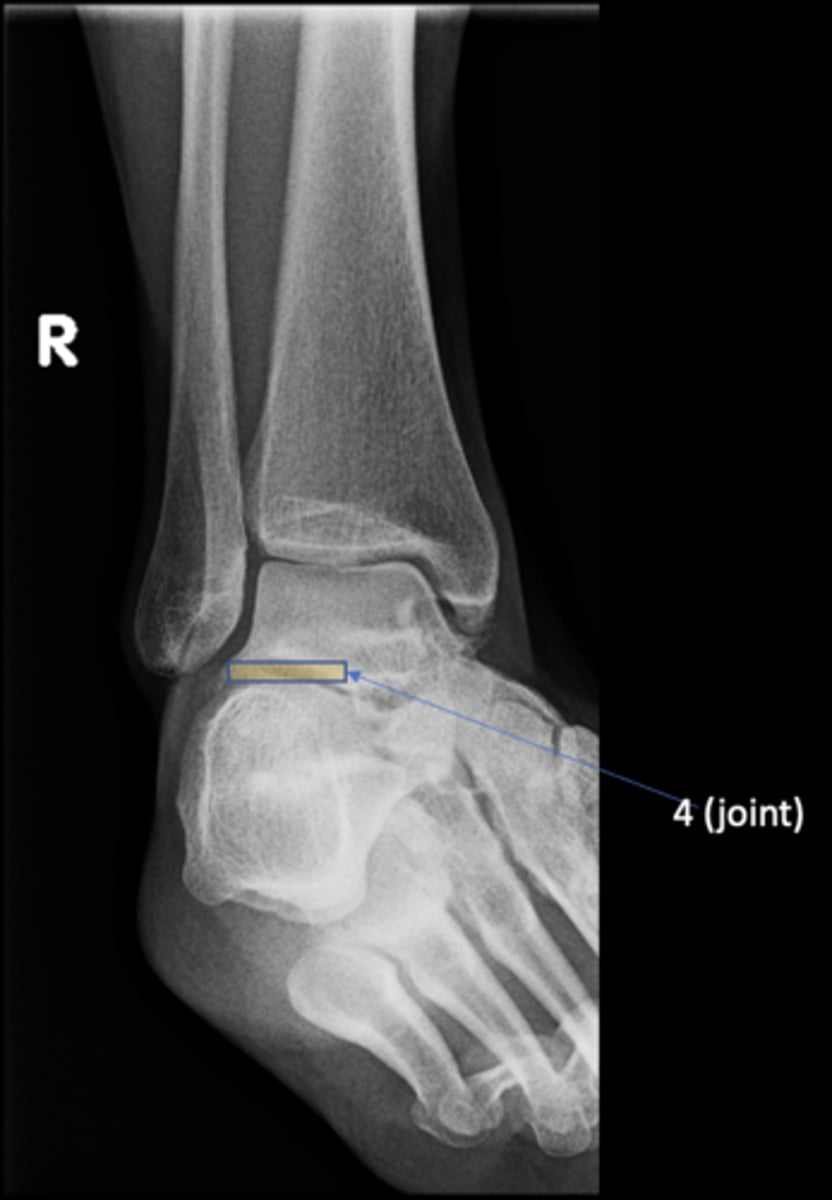

86

Talocalcaneal joint

<p>ID 4 (joint)</p>